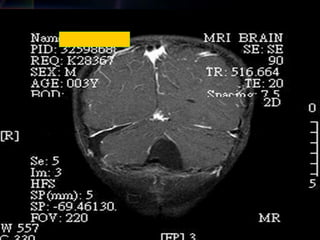

Quantec Radionik detected

a celleberum tumor

25

2013/12/7

32